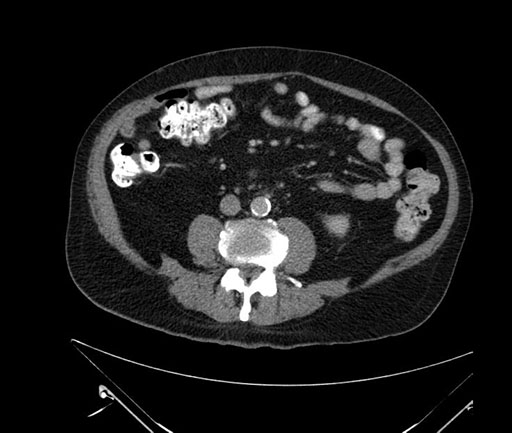

Imaging Analysis

Look through the patient's CT scan to identify any areas of concern for the necessary procedure.

Based on your CT findings, which issue(s) would give reason for "planned slowing down moment(s)" in this case?